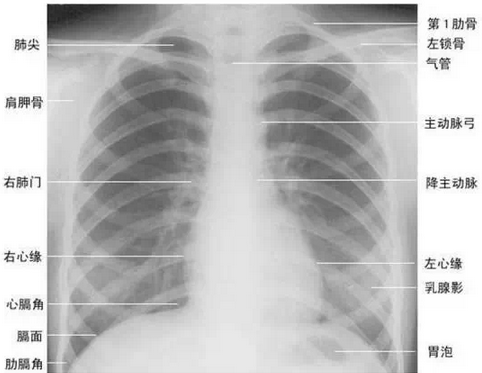

3.胸片或胸部CT检查:

胸片可以了解大概肺部有无结节,如有可疑结节,最好做胸部增强CT,进一步了解肺部情况,有无肺转移。关于X线片与CT的区别,有人比喻得很形象:

X光:像把面包压扁了看

X光会穿过人体,遇到被遮挡的部位,底片上不会曝光,洗片后这个部位就是白色的。

就像一片面包或一块棉花,看不到里面的纤维纹理,但用手压瘪了会清晰一些。X光最大缺点是受制于深浅组织的影像相互重叠和隐藏,有时需要多次多角度拍摄X光片。

CT:像把面包切片看

CT的检查原理是X光会分层穿过人体,之后通过电脑计算后二次成像,就像把一片面包切成片来看。优点是可以分层看,经计算后可以显示出更多的组织信息。